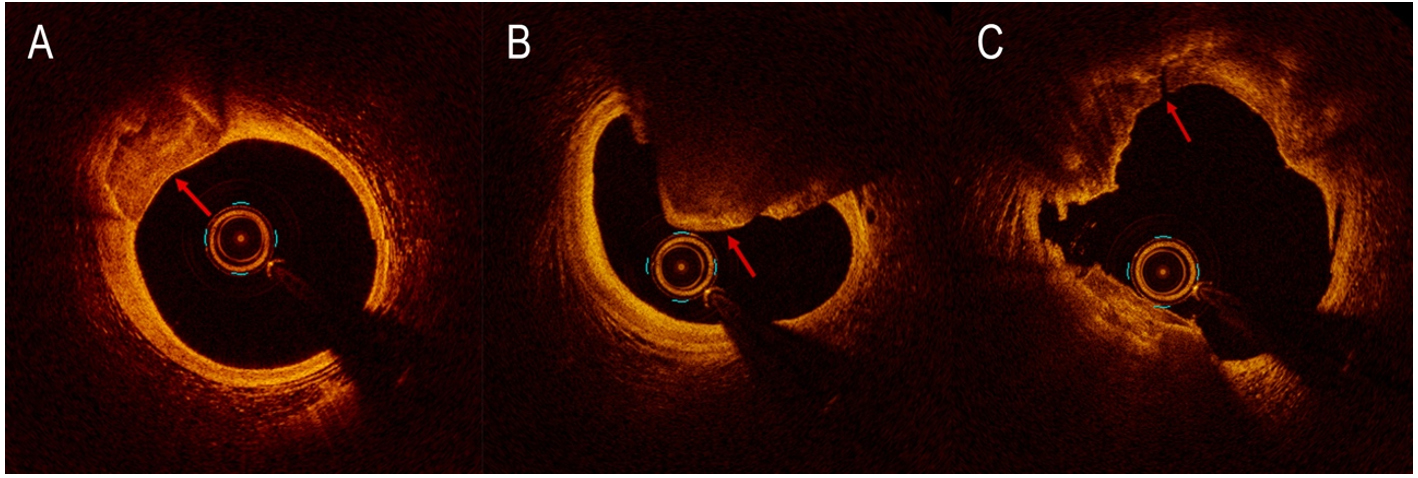

On optical coherence tomography (OCT) imaging, calcium appears thin, with a low-intensity signal area and well-delineated sharp borders[21] [Figure 4]. Thanks to its higher resolution (10 to 20 µm), OCT is able to quantify calcium thickness and show calcium disruption; its sensitivity and specificity for CAC are

Figure 4. Calcification detected by optical coherence tomography (OCT) as signal-poor area with well-delineated external contours (A). Nodular calcification detected by OCT (B). OCT reveals calcium fracture (red arrow) after the use of intravascular lithotripsy (C).

Figure 5. The OCT software (UltreonTM, Abbott, Illinois, US) is able to automatically measure the maximum calcium thickness and total angle of calcium (A). OCT can check the result, automatically calculating stent expansion and minimal stent area (B).

A recent study conducted by Fujino et al. presented an OCT score to classify calcium plaques with a numerical cut-off; calcium arc > 180° (2 points), calcium length

OCT disadvantages include injecting contrast medium to minimize light scatter from red blood cells, the possibility of missing deep calcifications due to insufficient penetration[21], and the potential misinterpretation of necrotic cores as calcium deposits[22].

Like IVUS, OCT is helpful in the planning of PCI, to choose a possible adjunctive intracoronary device dedicated to modify CAC by ablating its surface and breaking its integrity (fractures and discontinuities)[22]. OCT can check the effects of calcium debulking, identifying the presence of calcium fractures, which seem to be related to larger stent expansion and better procedural outcomes. The results of two recent studies suggested that CAC with extensive circumferential length and minor minimum axial thickness tended more to crack after conventional PCI[35,36]; these findings supported a dominant role of OCT in determining which calcium plaques need additional lesion preparation.

Finally, OCT can assess post-stent implantation by checking the presence of stent malapposition, measuring the distance between the abluminal surface of the strut and the luminal surface of the artery wall[37], edge dissections, and stent expansion [Figure 5B].

IVL has been extensively employed in the management of peripheral artery disease as a stand-alone tool and also to facilitate stent deployment. Single-arm, non-randomized clinical trials have assessed the safety and efficacy of IVL in the setting of CAD, in addition to coronary stenting[100,102,103]. The Disrupt CAD I was a prospective, multi-center, single-arm trial that included 60 patients with heavy calcifications of 21 mm average length and reached a 98,3% device success and a 92% residual stenosis < 30%[100]. MACE (composite of cardiac death, non-Q-wave MI, and target vessel revascularization (TVR) through 30 days) comprised only three patients (5%) with non-Q MI. The Disrupt CAD II was a prospective, multi-center trial that evaluated IVL treatment in 120 patients with heavy CAC of 25.7 mm in length. Acute lumen gain after only IVL was 0.83 ± 0.47 mm with residual stenosis of 32.7% ± 10.4%. Only 7.6% of patients experienced MACE at 30 days[103]. The OCT substudy conducted in 47 patients explained the principal mechanism of action of IVL by identifying calcium fractures in 78.7% of lesions[103]. The Disrupt CAD III was a prospective, single-arm, multi-center trial intended for regulatory authorization of coronary IVL that included 431 patients at 47 places in four countries; it demonstrated the safety and efficacy of the device. OCT substudy revealed multi-plane and longitudinal intraplaque fractures after IVL in 67.4% of CAC [Figure 4C]. MSA was

Eruptive CN is a form of CAC responsible for 2%-7% of acute coronary events. In a recent study conducted on patients with acute coronary syndrome (ACS) who had undergone pre-intervention OCT, three calcified culprit plaques were recognized: eruptive CN, superficial calcific sheet, and calcified protrusion[111]. Nodular calcification [Figure 4B] histologically consists of zones of calcification of variable dimensions, frequently accompanied by fibrin with a thick, integral fibrous cap. In eruptive CN, the fibrous cap is disrupted, with an overlying platelet/fibrin thrombus and no endothelium cells. These nodules are usually eccentric and can also disrupt the medial wall[112]. CN has been reported to be associated with stent failure, including ISR and stent thrombosis[113-115]. Nagata et al. have recently shown that the combined presence at OCT of eruptive CN and medial dissection with calcified flaps within the DES-implanted segment is correlated with a greater incidence of cumulative device-oriented composite endpoints (DoCE) after DES implantation[116]. The treatment of CN has not been established; however, RA is the preferred device in this setting because it can ablate the calcified structure within the CN, facilitating stent expansion. However, in a recent retrospective study, CN was associated with increased DoCE in patients treated with RA[117].